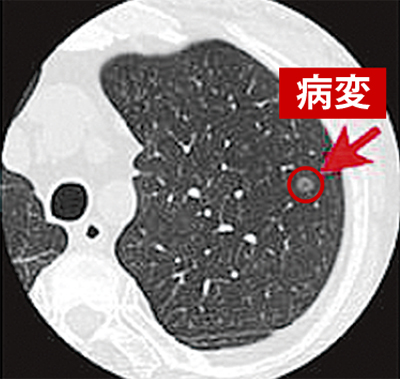

胸部エックス線(レントゲン)写真=写真左=では、肺の約3分の1は近接する臓器(心臓や血管、横隔膜など)と重なるため、小さな肺がんを見つけることが困難となる。一方、CT画像=写真右=は0・5㎜の厚さで横断像を撮影するため、重なりがなく、さらに分解能に優れるため、胸部エックス線には映らないような淡い陰影まで検出できる。「CT検診で発見した肺がんは86%以上が腫瘍3cm未満の早期で、5年生存率も90%と好成績を収めています」と平岩医師は話す。低線量肺がんCT検査料は9260円(税別)。